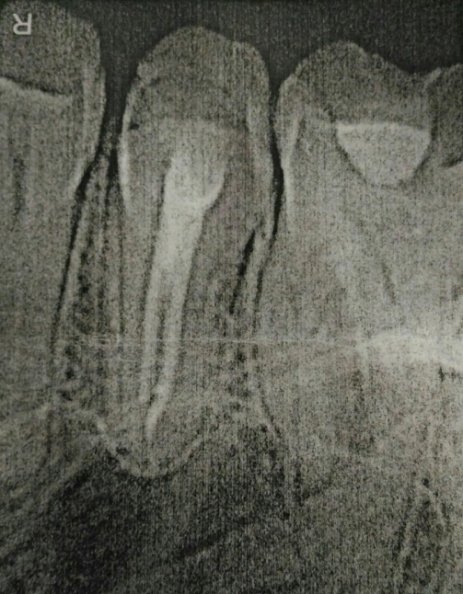

В подростковом возрасте мне сделали резекцию передних зубов из-за кисты. Но спустя примерно 15 лет над зубом образовался, на ощупь, шарик и очень неприятное напряжение под зубом. Я пошла к врачу, он отправил на снимок, но так и не смог мне помочь, и отправил к другому стоматологу, но попасть к нему я так и не смогла.

У вас так называемый рецидив. Обратитесь к хирургу, думаю, данный зуб придется удалить.